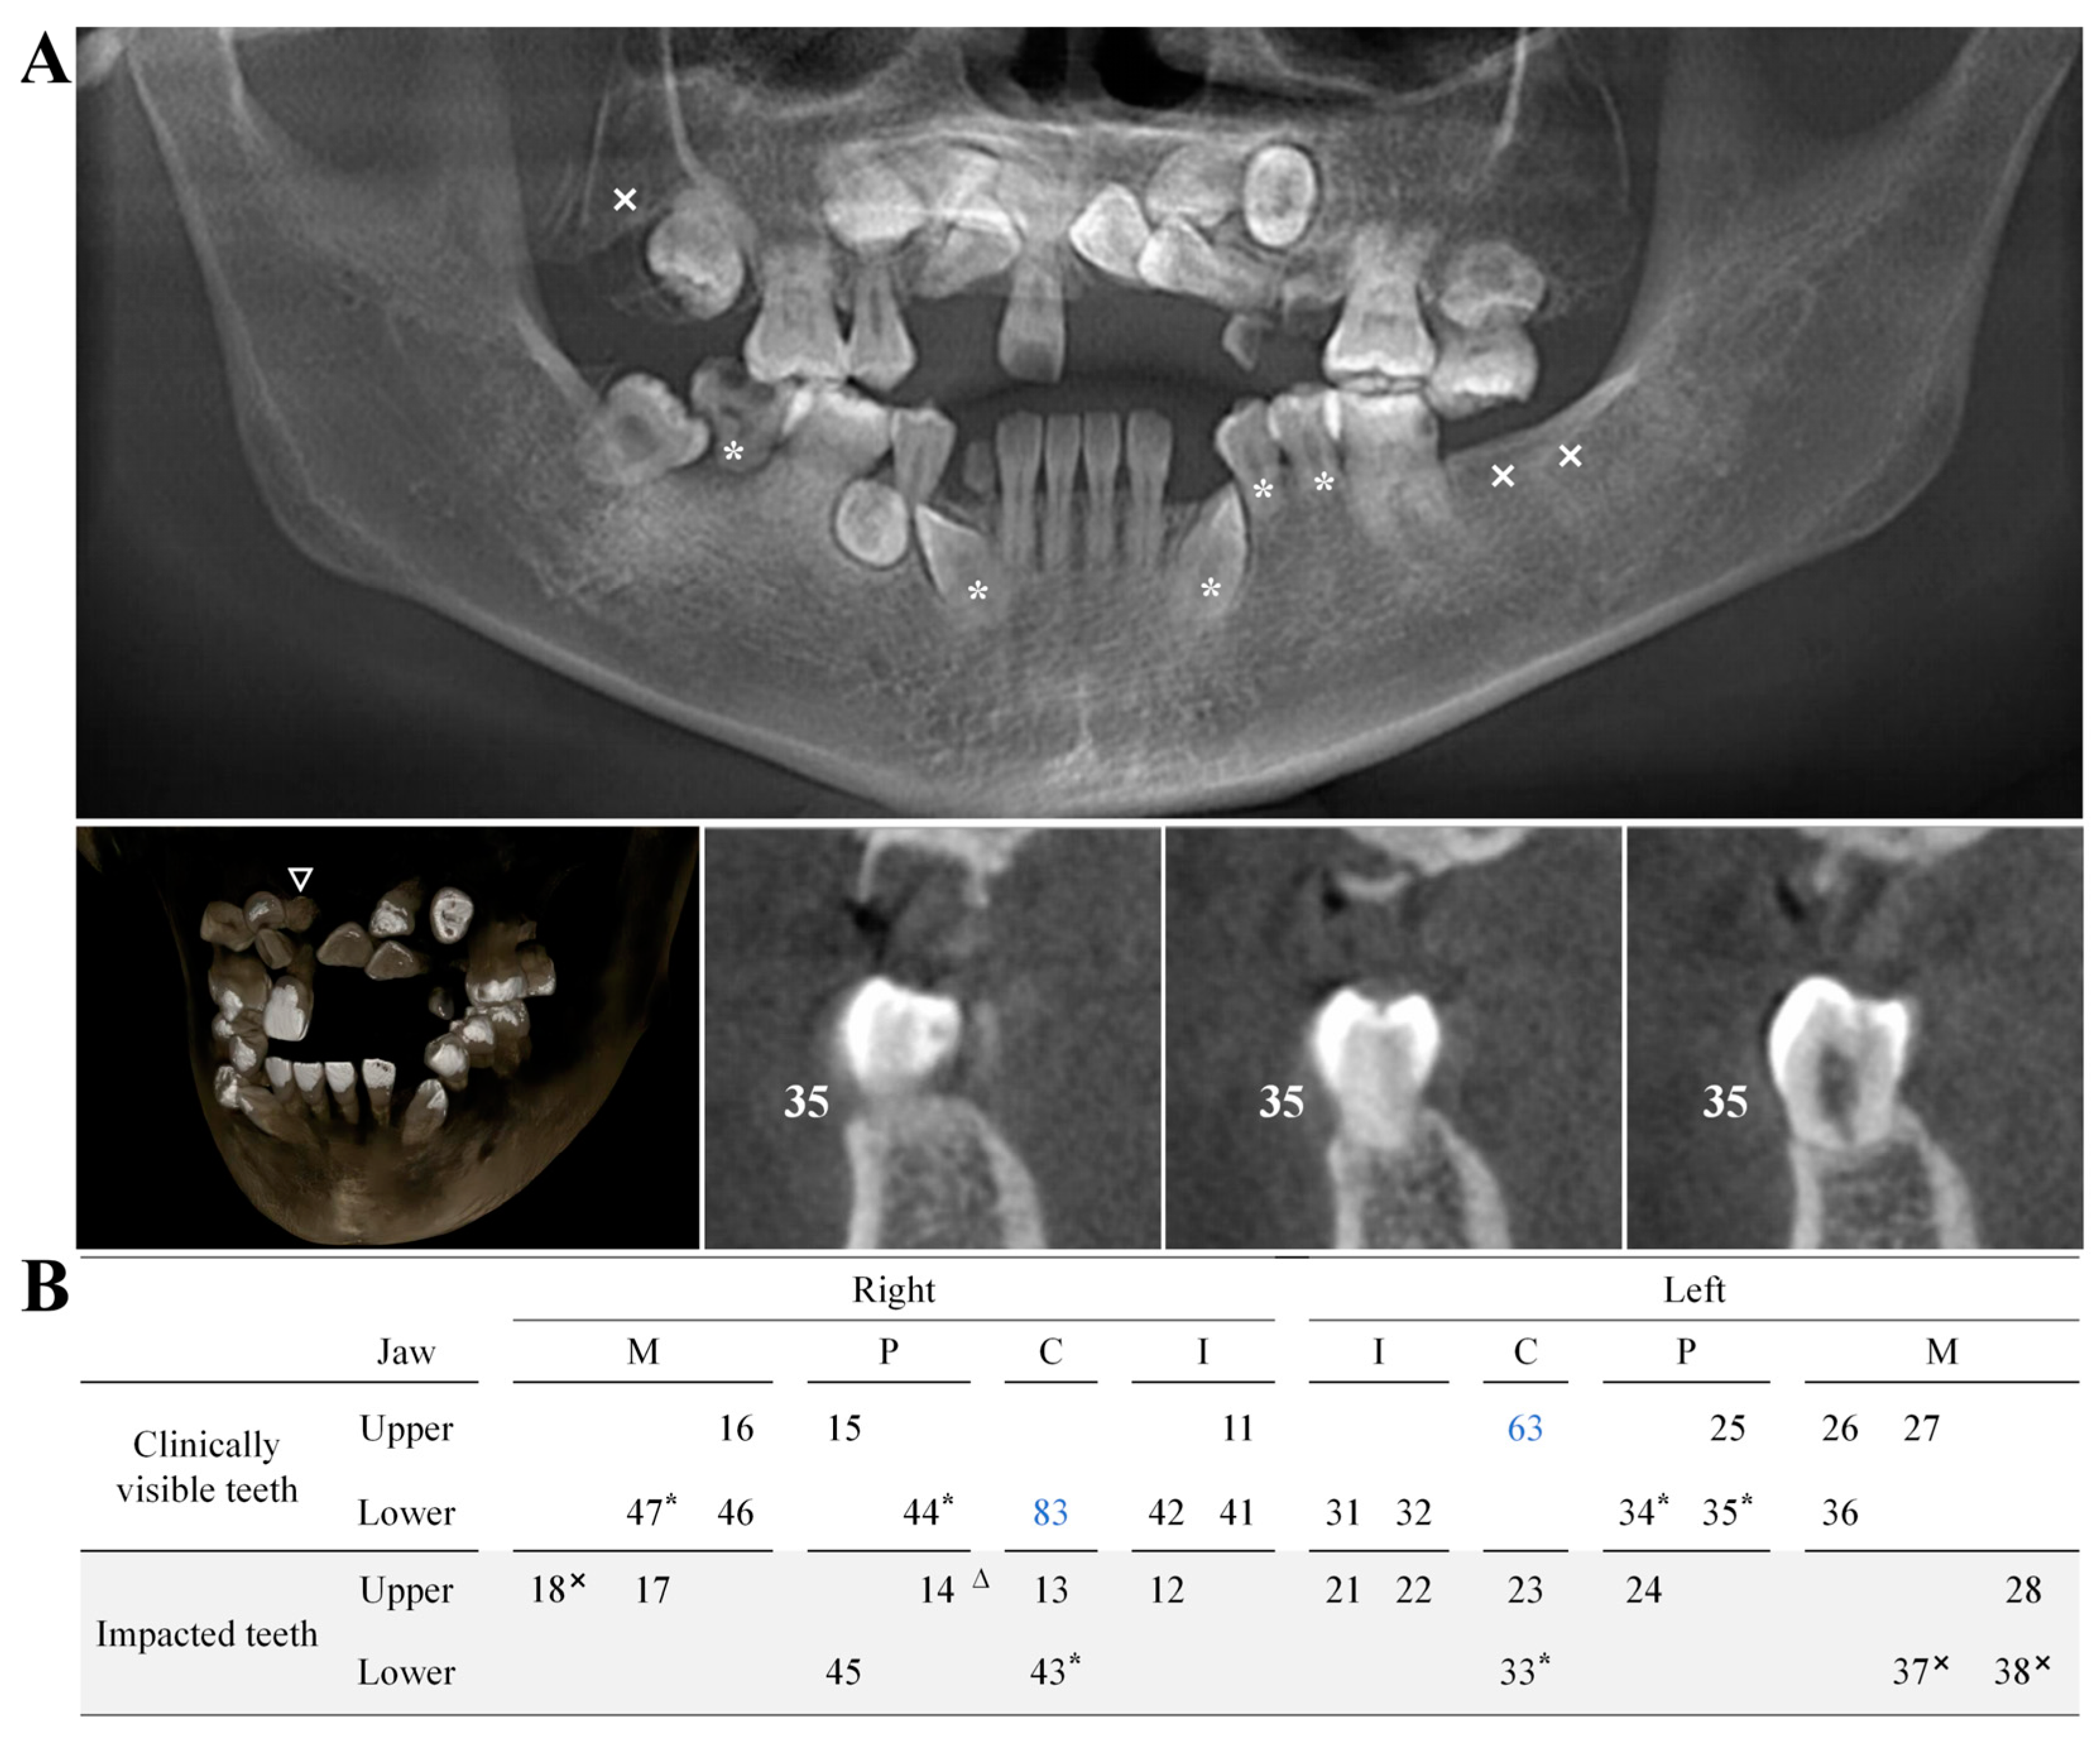

2.2. Biochemical and Radiographic Analysis